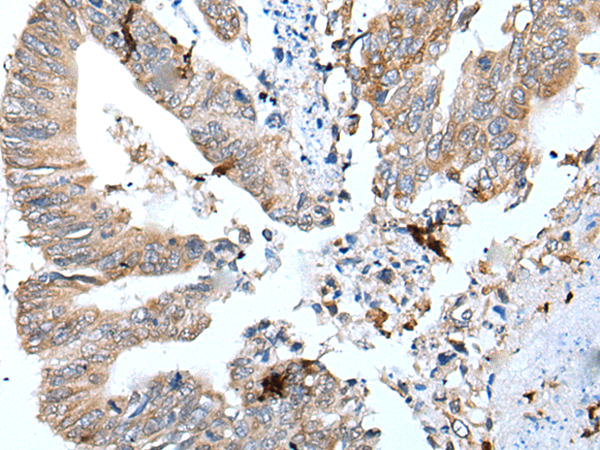

分类: 科研抗体货号: P12706别名: KHL4; DKELCHL应用: IHC反应种属: Human